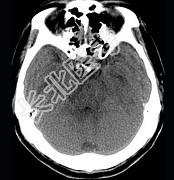

- 单项选择题男,57岁, 头痛、头晕1周,言语不清, 饮水呛咳两天,既往有鼻咽癌病史, 给予放射治疗,CT检查如图所示, 最可能的诊断是 ( )

A、放射性脑病

B、脑梗死

C、脱髓鞘病变

D、胶质瘤

E、脑炎